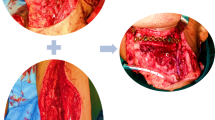

Case 6: Customized TMJ Reconstruction

A 55-year old man was referred for evaluation of his progressively worsening jaw function and progressive malocclusion. His past medical history was significant for rheumatoid arthritis that had affected multiple joints in his body including the TMJ’s. Clinical examination revealed severe mandibular retrusion and failure of previous TMJ reconstruction with extensive resorption of the mandibular rami bilaterally. Due to the destruction of the bilateral mandibular rami, it was decided to perform bone grafting to provide an adequate foundation for which to reconstruct the temporomandibular joint with TMJ prostheses. This patient’s 3-D model was extensively studied in order to determine the appropriate amount of advancement at pogonion that could be achieved, the appropriate mandibular ramus lengthening, and the deficit that would be created that would require bone grafting. Finally a wax-up was performed on the 3-D model to simulate the size and precise location of the cranial bone grafts needed (Fig. 6a). This exact simulation was replicated intraoperatively when placing the bone grafts and the TMJ prostheses (Fig. 6b). The fossa components were placed and secured with bone screws. The condylar prostheses were then secured to one of the cranial bone struts. A second cranial bone strut was then placed on the medial surface of the mandible. Bone screws were then placed through the prosthesis and both the medial and lateral bone grafts, thus sandwiching the native bone between the grafts. At the 9 years post-surgery follow-up examination, this patient had a stable occlusion, complete elimination of his obstructive sleep apnea, and a maximum inter-incisal opening of 33 mm [9].

a 3-D model has been waxed up to mimic normal bone contour of a mandibular ramus which has been destroyed multiple reconstructive surgical procedures in a patient affected with rheumatoid-induced TMJ disease. b Intraoperative view showing fixation of a patient-fitted, customized TMJ total joint replacement with an inlay cranial bone graft strut for simultaneous mandibular ramus reconstruction